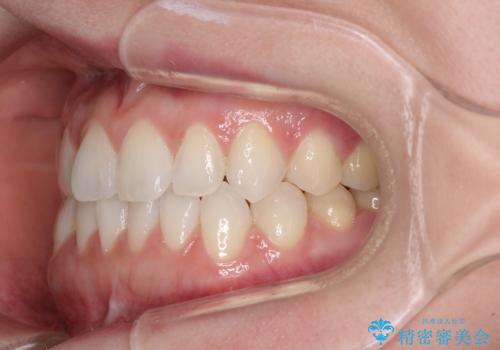

前歯のデコボコをすっきりと インビザライン矯正

- 前歯のデコボコを治したいとのことで来院された患者様です。

下顎が前方位にある方であったため、下顎の歯列全体の後方移動とIPR(歯と歯の間を削る)によってデコボコが解消するように設計し、インビザラインにより治療を行うこととしました。